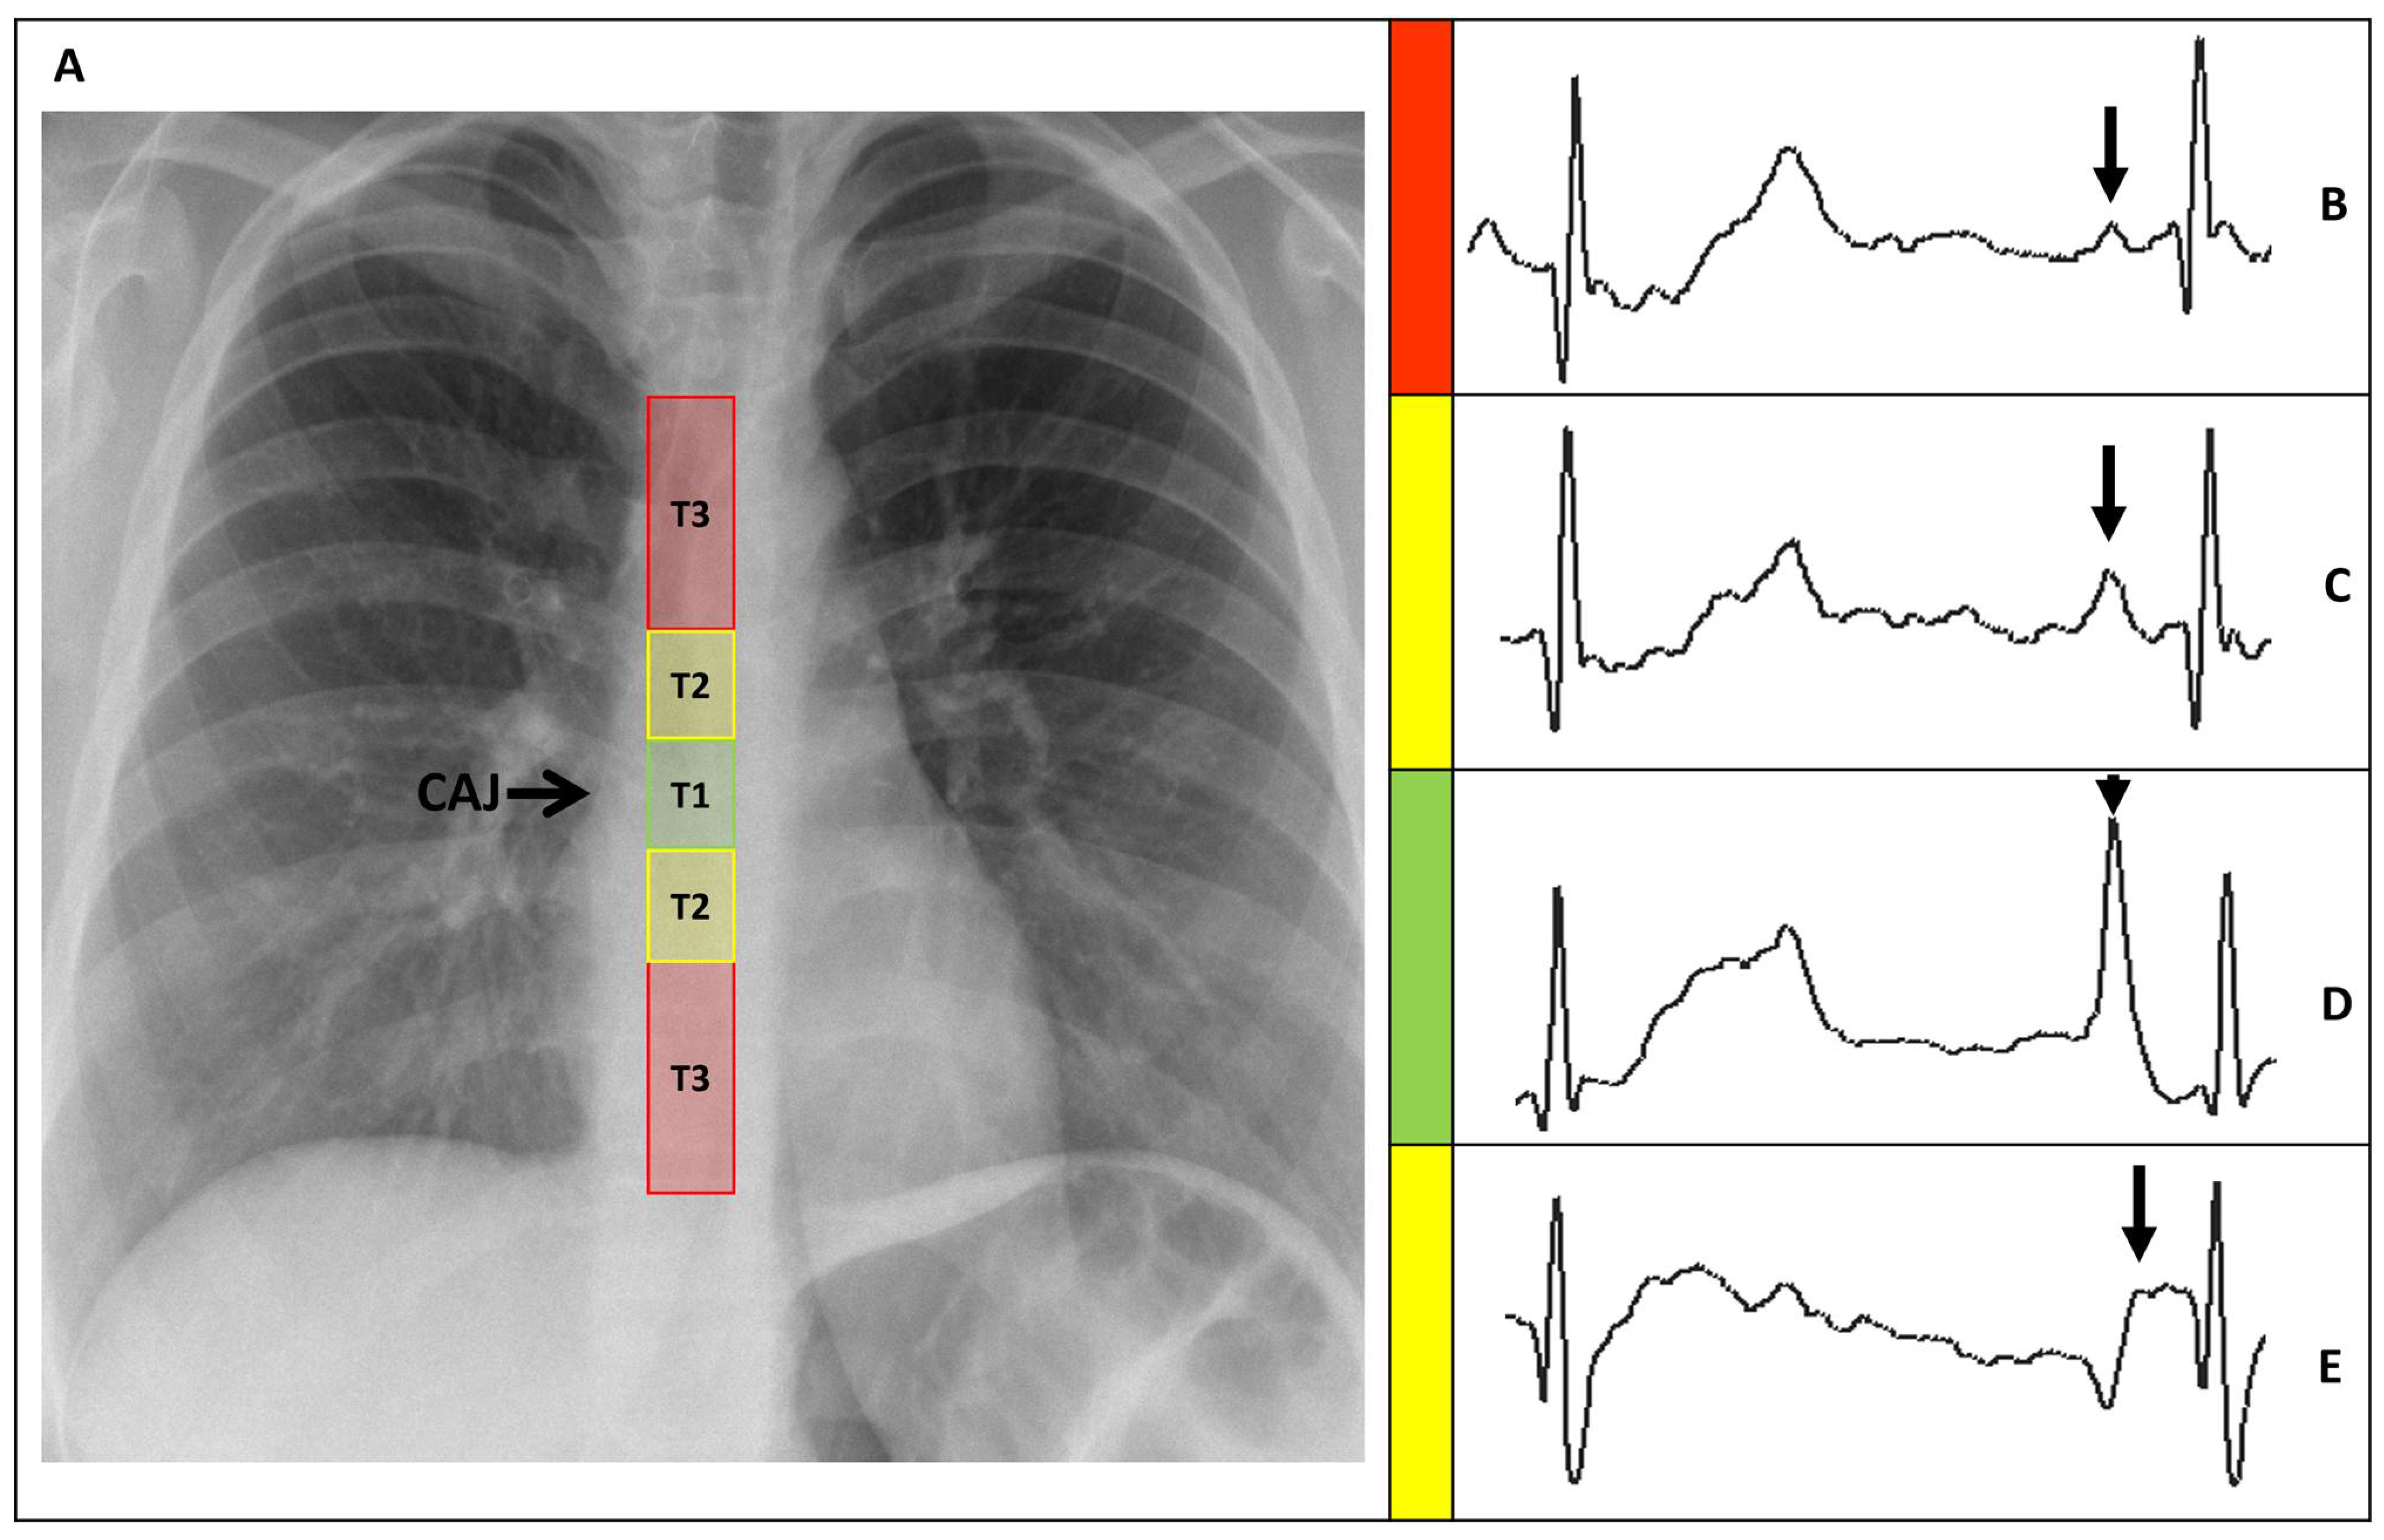

PICCs positions were classified, based on the distance between the catheter tip and the CAJ (DCAJ), as previously described and imaged [14]. The classifications were: T1: a final tip position of ±1 cm from the CAJ (optimal); T2: a tip position 1–3 cm above or below the CAJ (suboptimal); and T3: a tip position >3 cm below the CAJ or not in the SVC (inadequate, required repositioning) (Figure 3).

Figure 3.

(A) Chest X-ray showing the CAJ localization. The tip of the catheter in T1 (within 1 cm of the CAJ) is considered optimal (green zone). The tip in T2 (within 1–3 cm of the CAJ) is considered suboptimal (yellow zone). The tip in T3 (more than 3 cm below the CAJ or not in the SVC) is considered inadequate and needs to be repositioned (red zone). (B) Intracavitary electrocardiogram. A catheter tip in T3, distant from the SVC, will feature a trace similar to the superficial ECG trace, with a P-wave lower than the Twave immediately preceding it. (C) Intracavitary electrocardiogram. A catheter tip in T2, nearing the CAJ, will feature a trace with increasing P-wave, equaling the Twave immediately preceding it. (D) Intracavitary electrocardiogram. A catheter tip in T1, positioned at the CAJ level, will feature a P-wave with maximal amplitude without initial negative deflection. (E) Intracavitary electrocardiogram. A catheter tip in T2-T3, beyond the CAJ, will present a decreasing P-wave and negative deflection. CAJ, cavoatrial junction (open arrow); SVC, superior vena cava; P-wave (closed arrow).